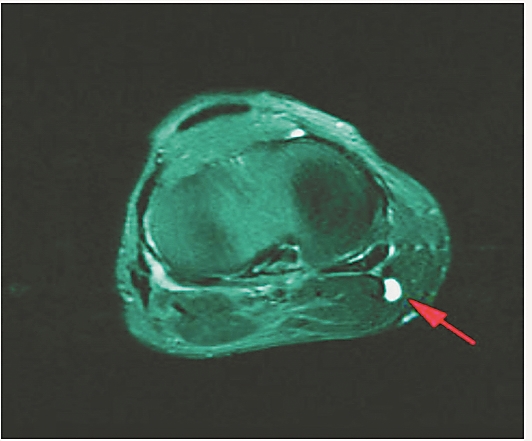

哈医大四院骨科专家逯代锋教授、刘慧敏医师、张春雨医师经过详细的体格检查和行膝关节磁共振检查后,诊断为左侧腘窝囊肿,在关节镜下成功为黄大爷进行了左膝关节镜检、腘窝囊肿内引流术。患者术后予以弹力绷带加压包扎,术后第1天开始锻炼患肢关节,并可下地行走。术后查房,黄大爷看到自己的手术切口后对逯代锋教授感激地说:“术前我就担心手术切口太长,没想到手术切口竟然不到1cm”。

据逯代锋教授介绍,腘窝囊肿的治疗,传统多采用后内侧开放手术切除腘窝囊肿,手术切口大,恢复周期长,而且由于不能同时处理关节腔内疾患,存在较高的复发率。随着膝关节镜技术的开展和成熟,关节镜治疗胭窝囊肿越来越多地应用于临床。关节镜手术不仅可以有效解决关节内疾患,而且可以打开腘窝囊肿的“阀门活瓣结构”,完整切除囊肿壁达到减压的目的和防止囊肿复发的效果。